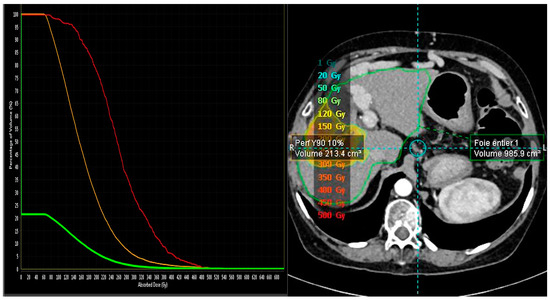

2.3. 90Y-Based Dosimetry Analysis

| Microsphere Type/Absorbed Tumor Dose | n/(Median and IQR) |

|---|---|

| SIRT Microsphere | 23 |

| SIR-Sphere | 15 |

| TheraSphere | 8 |

| Absorbed Tumor Dose | |

| SIR-Sphere | 268 Gy (107.1–243.2) |

| For complete and partial responses n = 11 | 167.4 Gy (127.7–243.2) |

| For stable or progression responses n = 4 | 79.6 Gy (50.7–183.7) |

| Thera-Sphere | 445 Gy (349.5–563.5) |

| For complete and partial responses n = 6 | 520 Gy (422.5–587.5) |

| For stable or progression responses n = 2 | 319 Gy (288.5–349.5) |